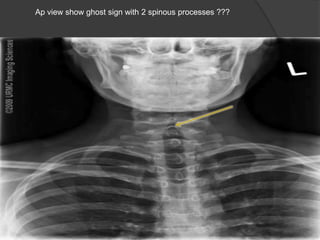

Ap view show ghost sign with 2 spinous processes ???

Ap view showghost sign with 2 spinous processes ???